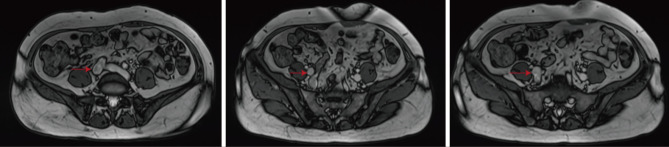

Case description: We report a case of retrogradely growing IVL, originating in the uterus and extending along the venous system to the right heart. At the same time, this leiomyomatosis retrogrades into the right external iliac vein. A 48-year-old woman with a mass in the IVC was admitted to Wuhan Union Hospital. She had undergone a hysterectomy for fibroids 2 years previously. Computed tomography venography and three-dimensional reconstruction revealed filling defects in the IVC, right internal and external iliac veins, right common iliac vein, right renal vein, and right atrium. After a multidisciplinary consultation, IVC leiomyomatosis was considered, and surgical treatment was performed.

Conclusions: We report a case of retrogradely growing IVL. It originates in the uterus, extends along the venous system to the right internal iliac vein, and grows retrogradely into the external iliac vein. This is a new growth path that has rarely been mentioned.